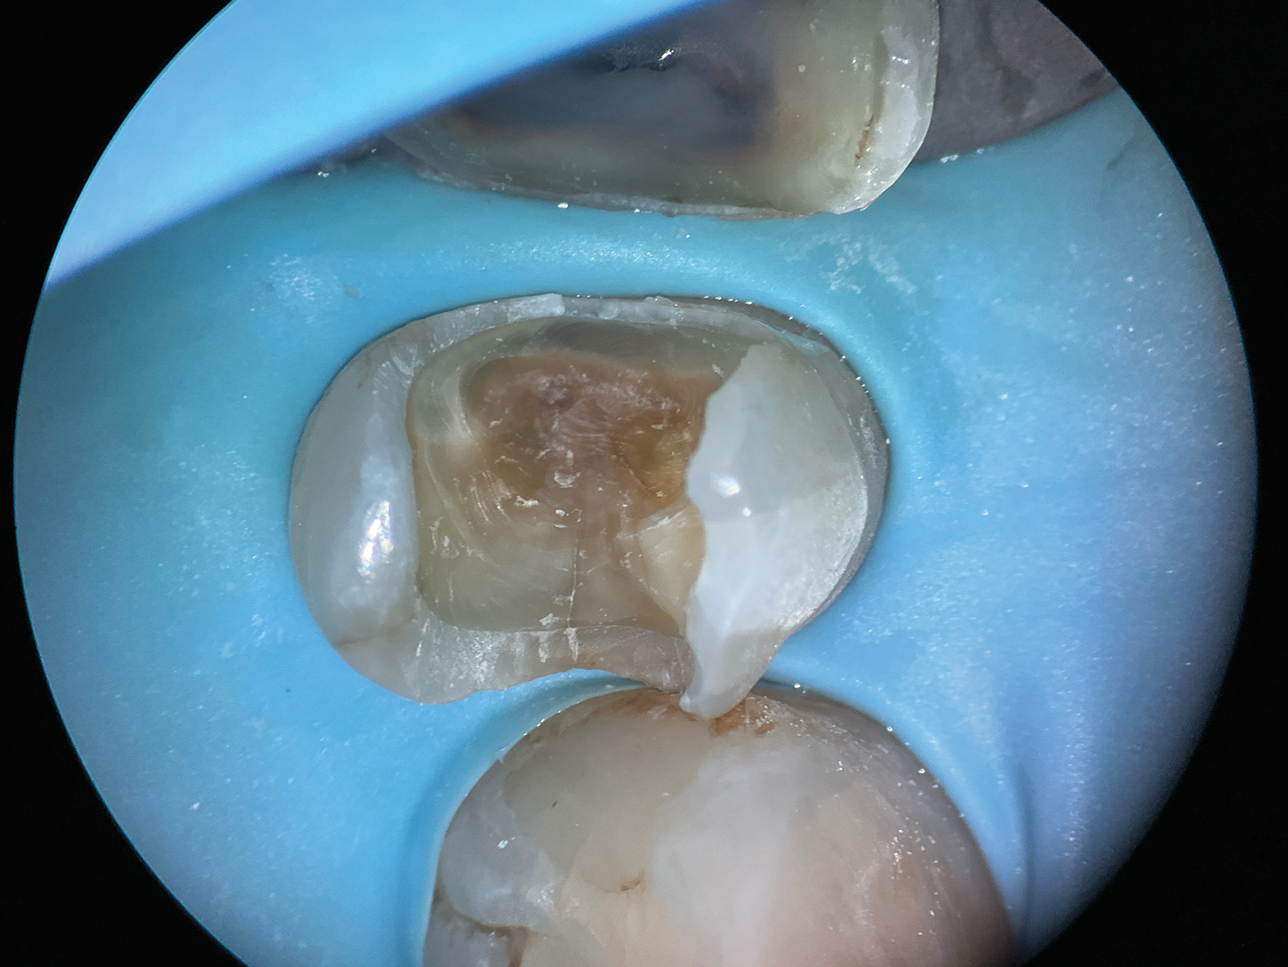

Extremely Deep Defects: Assisting Absolute Seal

In cases involving extremely deep defects that extend to the bone level, achieving an adequate seal and proper isolation for adhesive procedures can be particularly challenging (Figure 10 and Figure 11). Oftentimes, a single matrix proves insufficient to reach the depth of such defects and effectively shield the cavity from contamination by saliva or blood (Figure 12).

The matrix-in-matrix technique provides a practical and effective solution for these cases (Figure 13). By introducing a second matrix within the first, more specifically, a copper band that has been carefully cut and positioned inside a conventional matrix, the seal is significantly enhanced. This dual-layered approach not only extends the matrix coverage to the full depth of the defect for isolation but also ensures stability in the critical treatment area.

(10.) A close-up distolingual view of a mandibular molar after the removal of caries that extended to the bone level.

Figure 10

(11.) A Willems probe was used to determine that the depth of the margin was approximately 7 mm from the occlusal surface.

Figure 11

(12.) After subgingival placement of a Tofflemire matrix, despite using a wedge and adding additional support with polytetrafluoroethylene tape, fluid infiltration persists through the matrix and margin.

Figure 12

(13.) A wide 2-mil copper band was placed as an additional matrix to create absolute isolation, effectively sealing the space between the Tofflemire matrix and the margin.

Figure 13